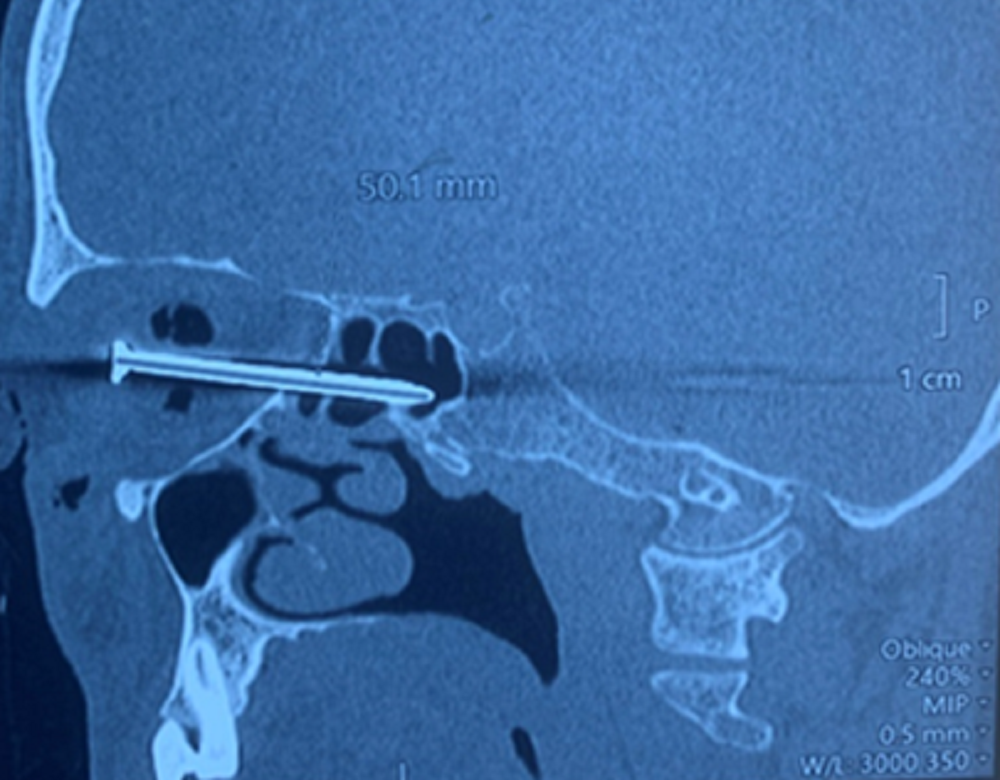

| Chiếc đinh xuyên vào hốc mắt khiến nạn nhân mất hoàn toàn thị lực mắt phải |

Từ các kết quả chẩn đoán hình ảnh, bác sĩ phát hiện dị vật là chiếc đinh kim loại xuyên ổ mắt bên phải, qua xoang sàng, xoang bướm; đầu nhọn của đinh đi cạnh trái khe thần kinh thị mắt phải và đầu nhọn nằm gần thành trái xoang bướm phải. Sau hội chẩn liên chuyên khoa, các bác sĩ quyết định phẫu thuật lấy dị vật.